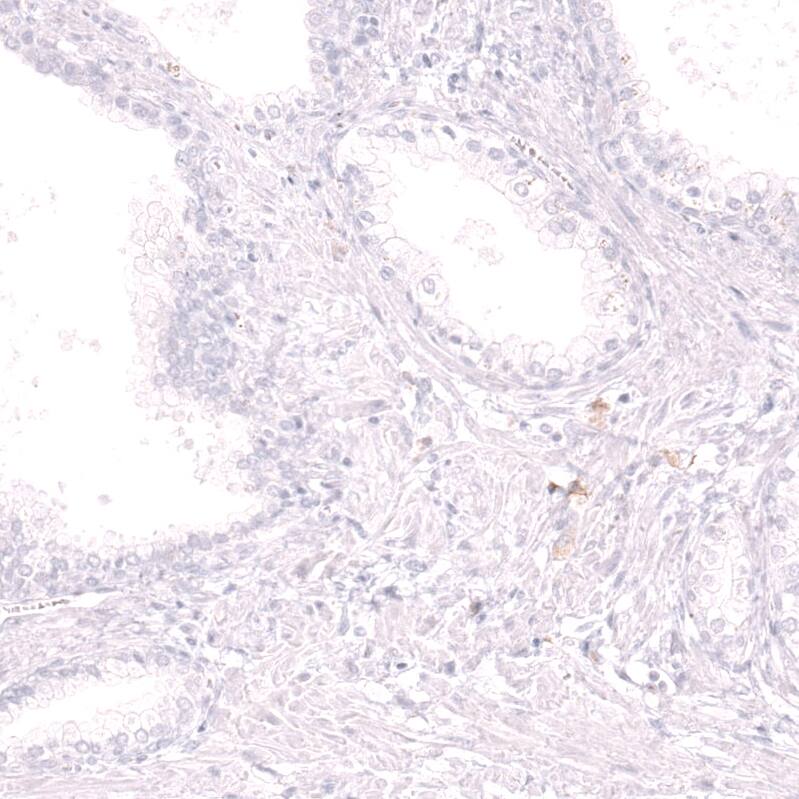

Immunohistochemistry-Paraffin: CD19 Antibody [NBP3-44277]

Staining of human kidney shows no positivity in cells in tubules as expected.